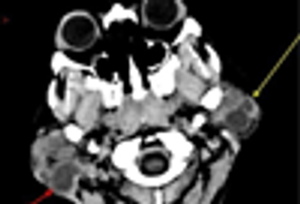

A large minority of persons with HIV infection have head and neck symptoms; parotid swellings have been noted in approximately 5% to 10% of patients with HIV-1 infection.